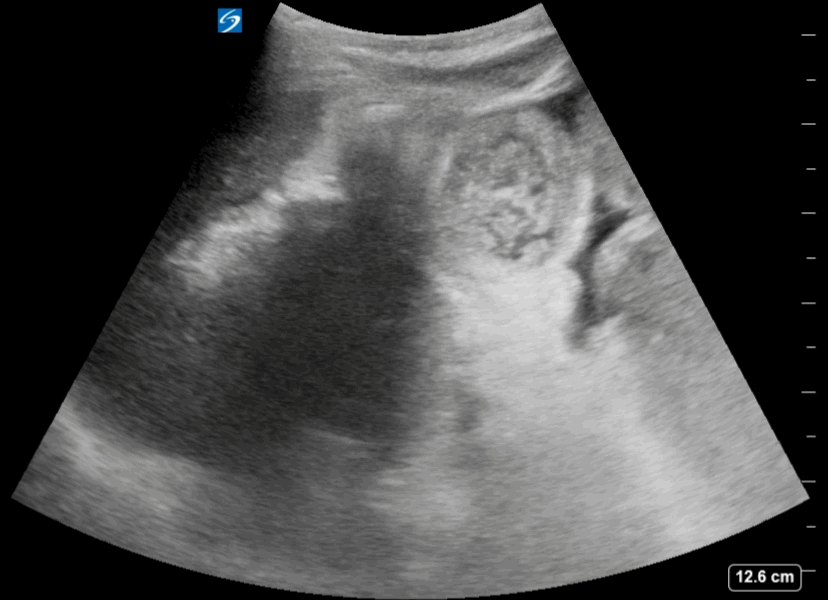

The video clip shows a small rim of free fluid along the liver edge with extensive free fluid noted amongst the intestinal loops

Free Fluid Around the Intestinal loops